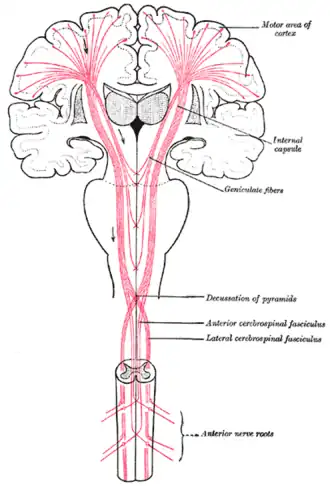

Причина любых церебральных параличей — патология в коре, подкорковых областях, в капсулах или стволе головного мозга[5]. Принципиальное отличие ДЦП от других параличей — во времени возникновения и связанном с этим нарушении редукции позотонических рефлексов, характерных для новорождённых.

Физиологические основы двигательного дефекта при детском церебральном параличе

Развитие спастики — при сохранении позотонических рефлексов из-за поражения головного мозга в определённый период его развития и сопутствующем нарушении становления цепных установочных выпрямительных рефлексов.